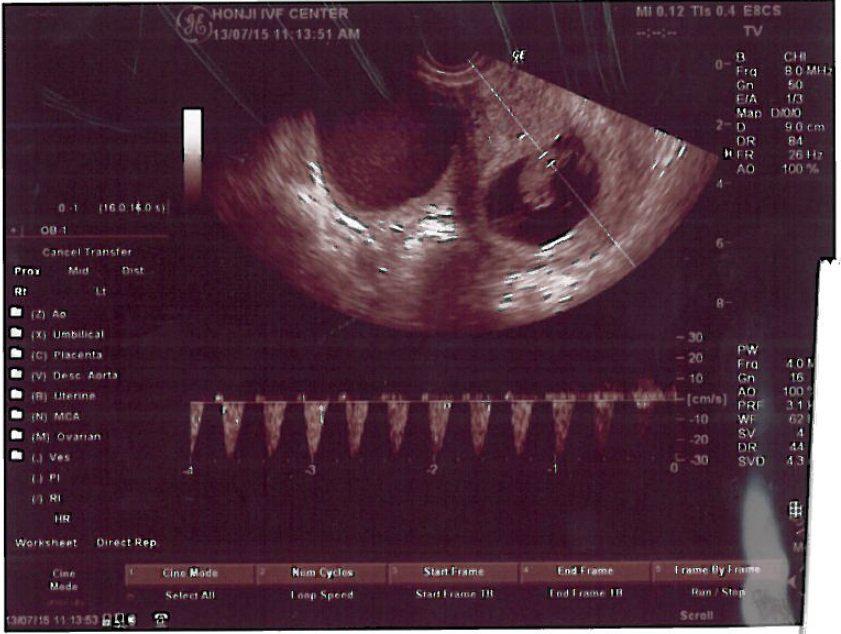

With the excellent quality control, few but accurate medicine in the early pregnancy, and data control of Doctor Chang and the lab team, my wife finally got pregnant this time. In the moment we heard the heartbeat of the baby, we understood the deep meaning of life! And it enlightens the karma would come magically in an unexpected moment!